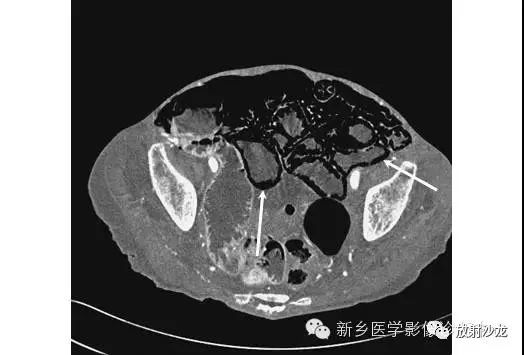

虽然X线平片足以诊断三分之二的肠壁积气病例,但CT可以更清楚地证明这种过程。CT上肠壁积气清晰可见(箭头)。